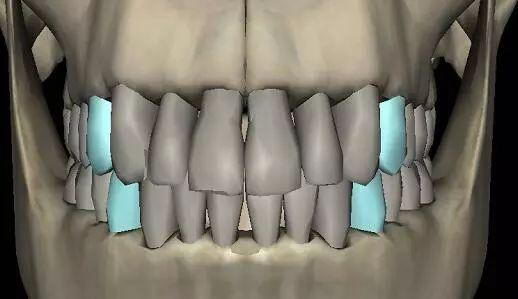

▲手术方案解析

矫正周期:术前牙齿矫正(6个月)+手术(1个月)+术后牙齿矫正(6个月)=13个月